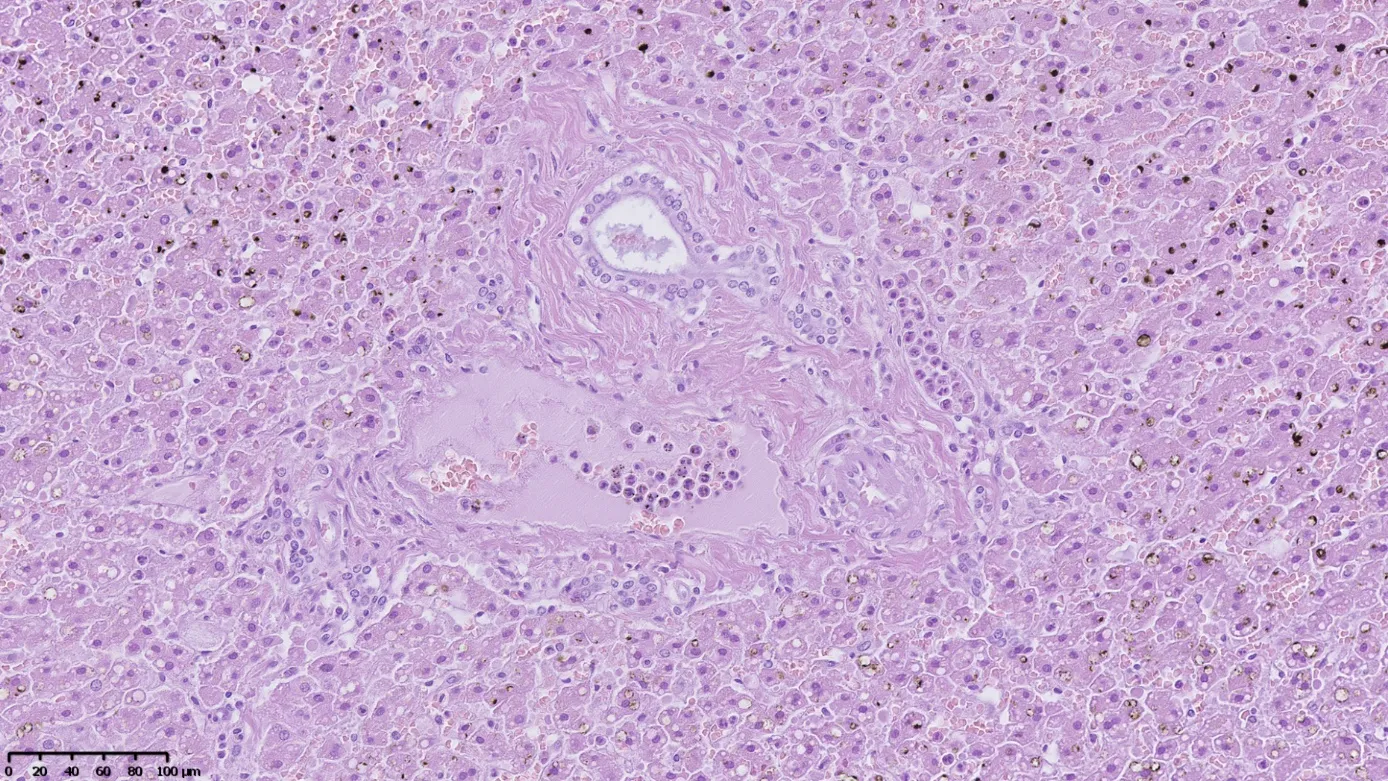

Morphological changes in the liver typically represent focal hepatocyte degeneration. Only in one case did they demonstrate signs of active inflammation and developing fibrosis (Figure 3). The nature of the observed changes does not allow for a clear connection with the use of “legal highs”, as the same changes may be associated with metabolic disorders, obesity, alcohol abuse, or viral hepatitis.

Figure 3. Numerous neutrophils are visible in the lumen of the venous vessel of the biliary space and in the dilated sinusoidal vessel. There is evidence of mild fibrosis of the biliary space and microvesicular steatosis of the hepatocytes. Numerous yellowish-brown artifacts associated with autolysis are visible in the upper and lower portions of the image. Hematoxilin & eosin stain, magnification ×200.